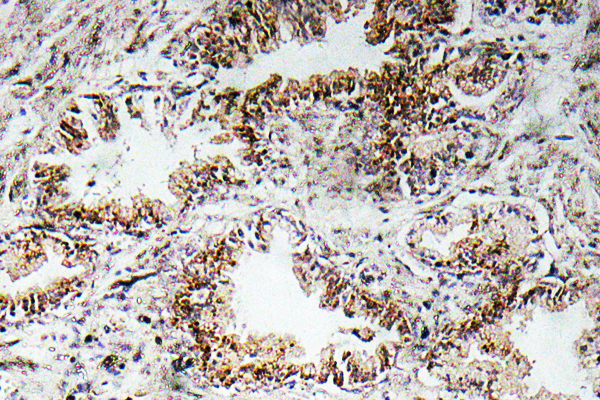

Main InformationTargetAChRα1Host SpeciesRabbitReactivityHuman, Mouse, RatApplicationsIHC, IF, ELISAMW55kD (Calculated)Conjugate/ModificationUnmodifiedDetailed InformationRecommended Dilution RatioIHC 1:100-1:300; ELISA 1:10000; IF 1:50-200FormulationLiquid in PBS containing 50% glycerol, 0.5% BSA and 0.02% sodium azide.SpecificityAChRα1 Polyclonal Antibody detects endogenous levels of AChRα1 protein.PurificationThe antibody was affinity-purified from rabbit antiserum by affinity-chromatography using epitope-specific immunogen.Storage-15°C to -25°C/1 year(Do not lower than -25°C)Concentration1 mg/mlMW(Calculated)55kDModificationUnmodifiedClonalityPolyclonalIsotypeIgGAntigen&Target InformationImmunogen:The antiserum was produced against synthesized peptide derived from human AChRalpha1. AA range:168-217Specificity:AChRα1 Polyclonal Antibody detects endogenous levels of AChRα1 protein.Gene Name:CHRNA1Protein Name:Acetylcholine receptor subunit alphaOther Name:CHRNA1 ; ACHRA ; CHNRA ; Acetylcholine receptor subunit alphaDatabase Link:Background:The muscle acetylcholine receptor consiststs of 5 subunits of 4 different types: 2 alpha subunits and 1 each of the beta, gamma, and delta subunits. This gene encodes an alpha subunit that plays a role in acetlycholine binding/channel gating. Alternatively spliced transcript variants encoding different isoforms have been identified. [provided by RefSeq, Nov 2012],Function:Disease:Defects in CHRNA1 are a cause of congenital myasthenic syndrome fast-channel type (FCCMS) [MIM:608930]. FCCMS is a congenital myasthenic syndrome characterized by kinetic abnormalities of the AChR. In most cases, FCCMS is due to mutations that decrease activity of the AChR by slowing the rate of opening of the receptor channel, speeding the rate of closure of the channel, or decreasing the number of openings of the channel during ACh occupancy. The result is failure to achieve threshold depolarization of the endplate and consequent failure to fire an action potential.,Disease:Defects in CHRNA1 are a cause of congenital myasthenic syndrome slow-channel type (SCCMS) [MIM:601462]. SCCMS is the most common congenital myasthenic syndrome. Congenital myasthenic syndromes are characterized by muscle weakness affecting the axial and limb muscles (with hypotonia in early-onset forms), the ocular muscles (leading to ptosis and ophthalmoplegia), and the facial and bulbar musculature (affecting sucking and swallowing, and leading to dysphonia). The symptoms fluctuate and worsen with physical effort. SCCMS is caused by kinetic abnormalities of the AChR, resulting in prolonged endplate currents and prolonged AChR channel opening episodes.,Disease:Defects in CHRNA1 are a cause of lethal type multiple pterygium syndrome [MIM:253290]. Multiple pterygia are found infrequently in children with arthrogryposis and in fetuses with fetal akinesia syndrome. In lethal multiple pterygium syndrome there is intrauterine growth retardation, multiple pterygia, and flexion contractures causing severe arthrogryposis and fetal akinesia. Subcutaneous edema can be severe, causing fetal hydrops with cystic hygroma and lung hypoplasia. Oligohydramnios and facial anomalies are frequent.,Disease:The alpha subunit is the main focus for antibody binding in myasthenia gravis [MIM:254200]. Myasthenia gravis is characterized by sporadic muscular fatigability and weakness, occurring chiefly in muscles innervated by cranial nerves, and characteristically improved by cholinesterase-inhibiting drugs.,Function:After binding acetylcholine, the AChR responds by an extensive change in conformation that affects all subunits and leads to opening of an ion-conducting channel across the plasma membrane.,similarity:Belongs to the ligand-gated ionic channel (TC 1.A.9) family.,subunit:Pentamer of two alpha chains, and one each of the beta, delta, and gamma (in immature muscle) or epsilon (in mature muscle) chains.,tissue specificity:Isoform 1 is only expressed in skeletal muscle whereas isoform 2 is constitutively expressed in skeletal muscle, brain, heart, kidney, liver, lung and thymus.,Cellular Localization:Cell junction, synapse, postsynaptic cell membrane ; Multi-pass membrane protein . Cell membrane ; Multi-pass membrane protein .Tissue Expression:Isoform 1 is only expressed in skeletal muscle. Isoform 2 is constitutively expressed in skeletal muscle, brain, heart, kidney, liver, lung and thymus.Research Areas:>>Neuroactive ligand-receptor interaction